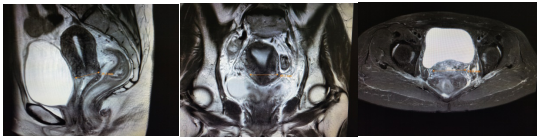

该患者诊断明确,为中晚期宫颈癌,依据现有指南,治疗原则为同步放化疗,放疗包括外照射放疗和腔内近距离放疗。外照射放疗技术选择动态调强放疗(VMAT),盆腔淋巴结引流区剂量5040cGy/28F,阳性淋巴结剂量5992cGy/28F,同期给予铂类同步化疗,1次/周。外照射结束前1周内复查盆腔核磁(图2):宫颈肿块较前明显缩小;两侧髂血管走行区、左侧闭孔区、骶前脂肪间隙内转移淋巴结较前缩小。

外照射放后近距离放疗前盆腔核磁